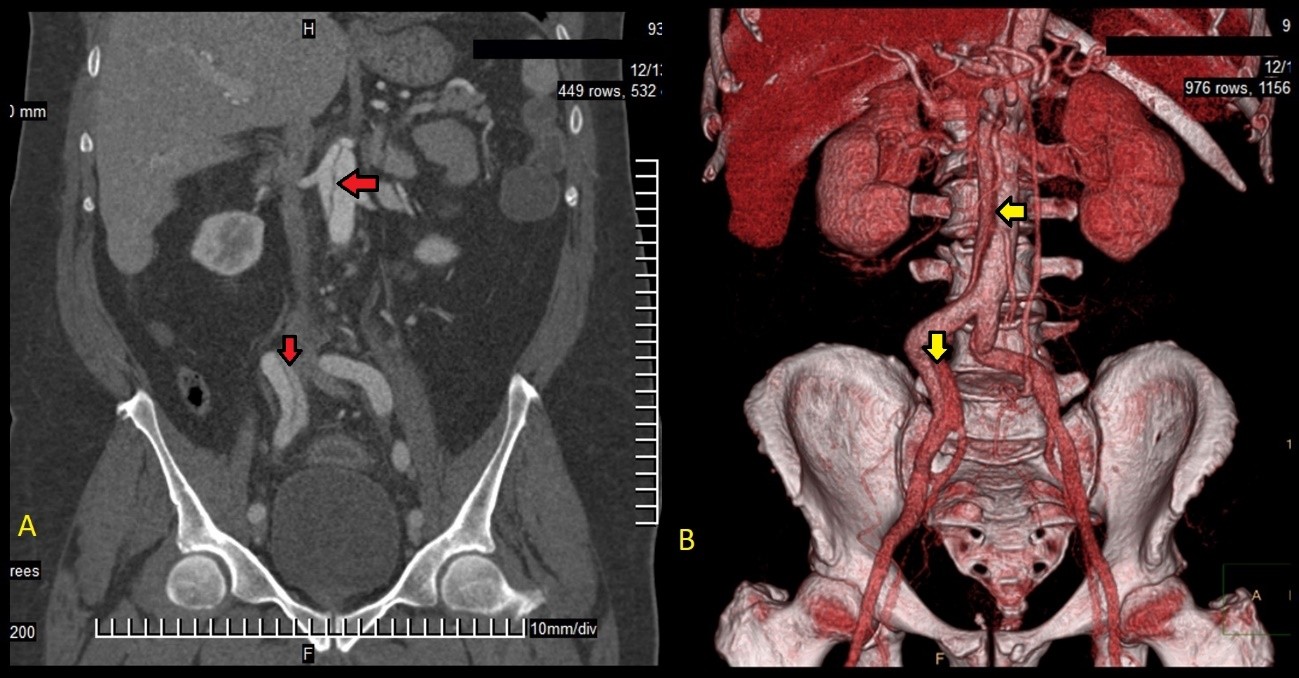

En la tomografía con cortes axial y coronal se observó el colgajo íntimo que dividía la luz aórtica en falsa y verdadera, aunque sin ocluirla. La disección comprometía la aorta ascendente, el arco aórtico, y aorta abdominal, y se extendía a las arterias renal derecha e ilíaca ipsilateral. Se constató derrame pericárdico leve (Fig. 2-4).

Fig. 3 -Comparación entre la tomografía abdominal en corte coronal (A) y la reconstrucción tridimensional mediante tomografía angiográfica contrastada (B). Obsérvese el recorrido disecante (flechas rojas en A y amarillas en B).